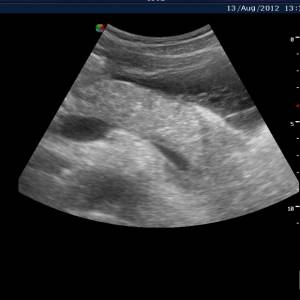

В норме поджелудочная железа расположена в области эпигастрия и имеет следующие эхо признаки.

- По форме бывает «колбасовидная», «гантелевидная» или на подобии «головастика».

- Очертания должны быть ровные, четкие, с отграничением от окружающих тканей.

- Нормальные размеры железы у взрослых: головка – 18-28 мм, тело 8-18 мм, хвост 22-29 мм. У детей размеры зависят от их роста и колеблются в следующих пределах: головка – 10-21 мм, тело – 6-13 мм, хвост – 10-24 мм.

- Эхогенность, т.е. отражающая способность – средняя (сопоставима с эхогенностью неизмененной печени). С возрастом она становится повышенной.

- Эхо структура однородная (гомогенная, мелкозернистая или крупнозернистая).

- Сосудистый рисунок – без деформации.

- Вирсунгов проток – не расширен (диаметр его в норме 1,5-2,5 мм).